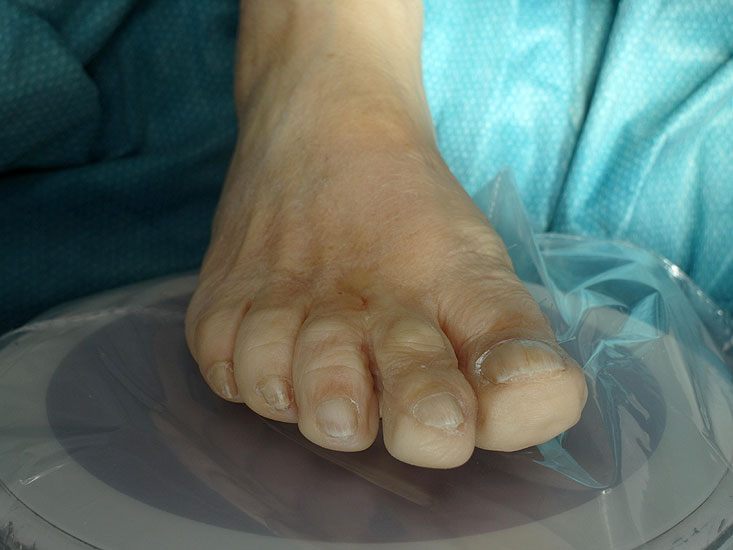

Abwaschen und steriles Abdecken des Fußes und Sprunggelenkes, die Operation erfolgt in der Regel ohne Blutleere. Der Bildwandler steht am Fußende, in Längsrichtung zum Patienten geneigt, der Patientenfuß kann  leicht auf dem Röntgendetektor aufliegen. Die orthograde Ausrichtung des Fusses, erreicht durch eine Unterpolsterung der gleichseitigen Glutealregion ist zu empfehlen. Der Operateur steht oder sitzt in Längsrichtung des Patienten hinter dem Röntgendetektor. So können die mehrfach nötigen Bildwandlerkontrollen unkompliziert und zeitsparend durchgeführt werden (Abb 3).